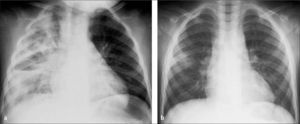

b)Neumonía intersticialEl patrón intersticial se observa con frecuencia en infecciones virales. Histológicamente, en el compromiso intersticial se evidencia inflamación del epitelio bronquial y edema del tejido intersticial, cambios que producen mayoritariamente los virus (1).

Este compromiso se observa en Rx simple como aparición de opacidades peribronquiales que adoptan un aspecto radiado desde el hilio pulmonar hacia la periferia; la medida que estos cambios progresan, el patrón se hace más confluente. La presencia de edema e infiltrados celulares en los espacios peribronquiales produce disminución de calibre y obstrucción de la vía aérea, lo que determina aparición de dos hallazgos importantes que habitualmente se asocian a la neumopatía intersticial: hiperinsuflación y atelectasias (1).

La hiperinsuflación es consecuencia del mecanismo de válvula que se produce en espiración en la vía aérea inflamada, hecho que se acentúa en la edad pediátrica por su escaso calibre, generando atrapamiento aéreo con aumento de la transparencia del parénquima pulmonar. La proyección lateral es de gran utilidad para valorar el aumento del diámetro antero-posterior, aplanamiento diafragmático y aumento de transparencia del espacio retroesternal, como signos de hiperinsuflación (Figura 7). En los niños es frecuente observar atelectasias, especialmente subsegmentarias, por el menor desarrollo de la ventilación colateral en el pulmón infantil (canales de Lambert y poros de Kohn). Estas atelectasias aparecen como bandas lineales, densas, pequeñas, de contornos bien definidos, visibles especialmente en las regiones medias inferiores de los pulmones. En niños mayores es posible observar también atelectasias segmentarias o lobares, con un patrón anatómico similar al que se observa en adultos (4).